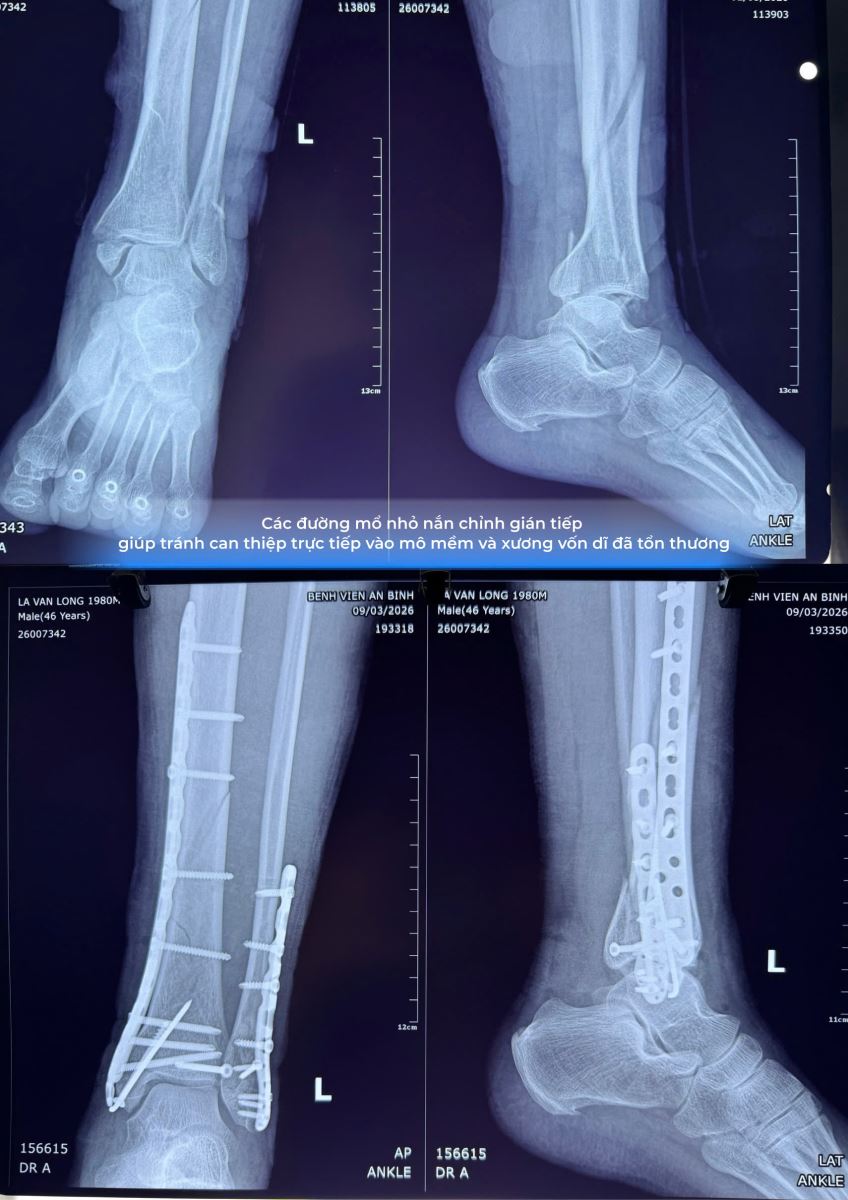

Qua thăm khám lâm sàng và các phương tiện chẩn đoán hình ảnh như X-quang và CT scanner, các bác sĩ xác định bệnh nhân bị gãy phức tạp 3 mắt cá chân, gãy 1/3 dưới xương chày, bán trật khớp cổ chân, rối loạn dinh dưỡng mô mềm và viêm mô bào do đắp thuốc.

Xquang cho thấy gãy phức tạp ba mắt cá, bán trật khớp cổ chân kèm gãy 1/3 dưới xương chày. Ảnh: BV

Giai đoạn đầu tập trung kiểm soát nhiễm trùng và ổn định mô mềm, ưu tiên xử lý tình trạng viêm mô bào và phục hồi vùng da tổn thương trước khi can thiệp vào xương. Sau khi tình trạng mô mềm ổn định, bệnh nhân được phẫu thuật kết hợp xương bằng kỹ thuật xâm lấn tối thiểu.

“Thay vì thực hiện các đường mổ lớn để bộc lộ ổ gãy theo phương pháp truyền thống, kíp phẫu thuật sử dụng các đường mổ nhỏ nhằm hạn chế tác động lên vùng xương và mô mềm đã bị tổn thương. Phương pháp này giúp giảm nguy cơ hoại tử da, hạn chế tổn thương mô mềm và hỗ trợ quá trình phục hồi sau phẫu thuật”, bác sĩ Phạm Văn Nhật cho biết thêm.